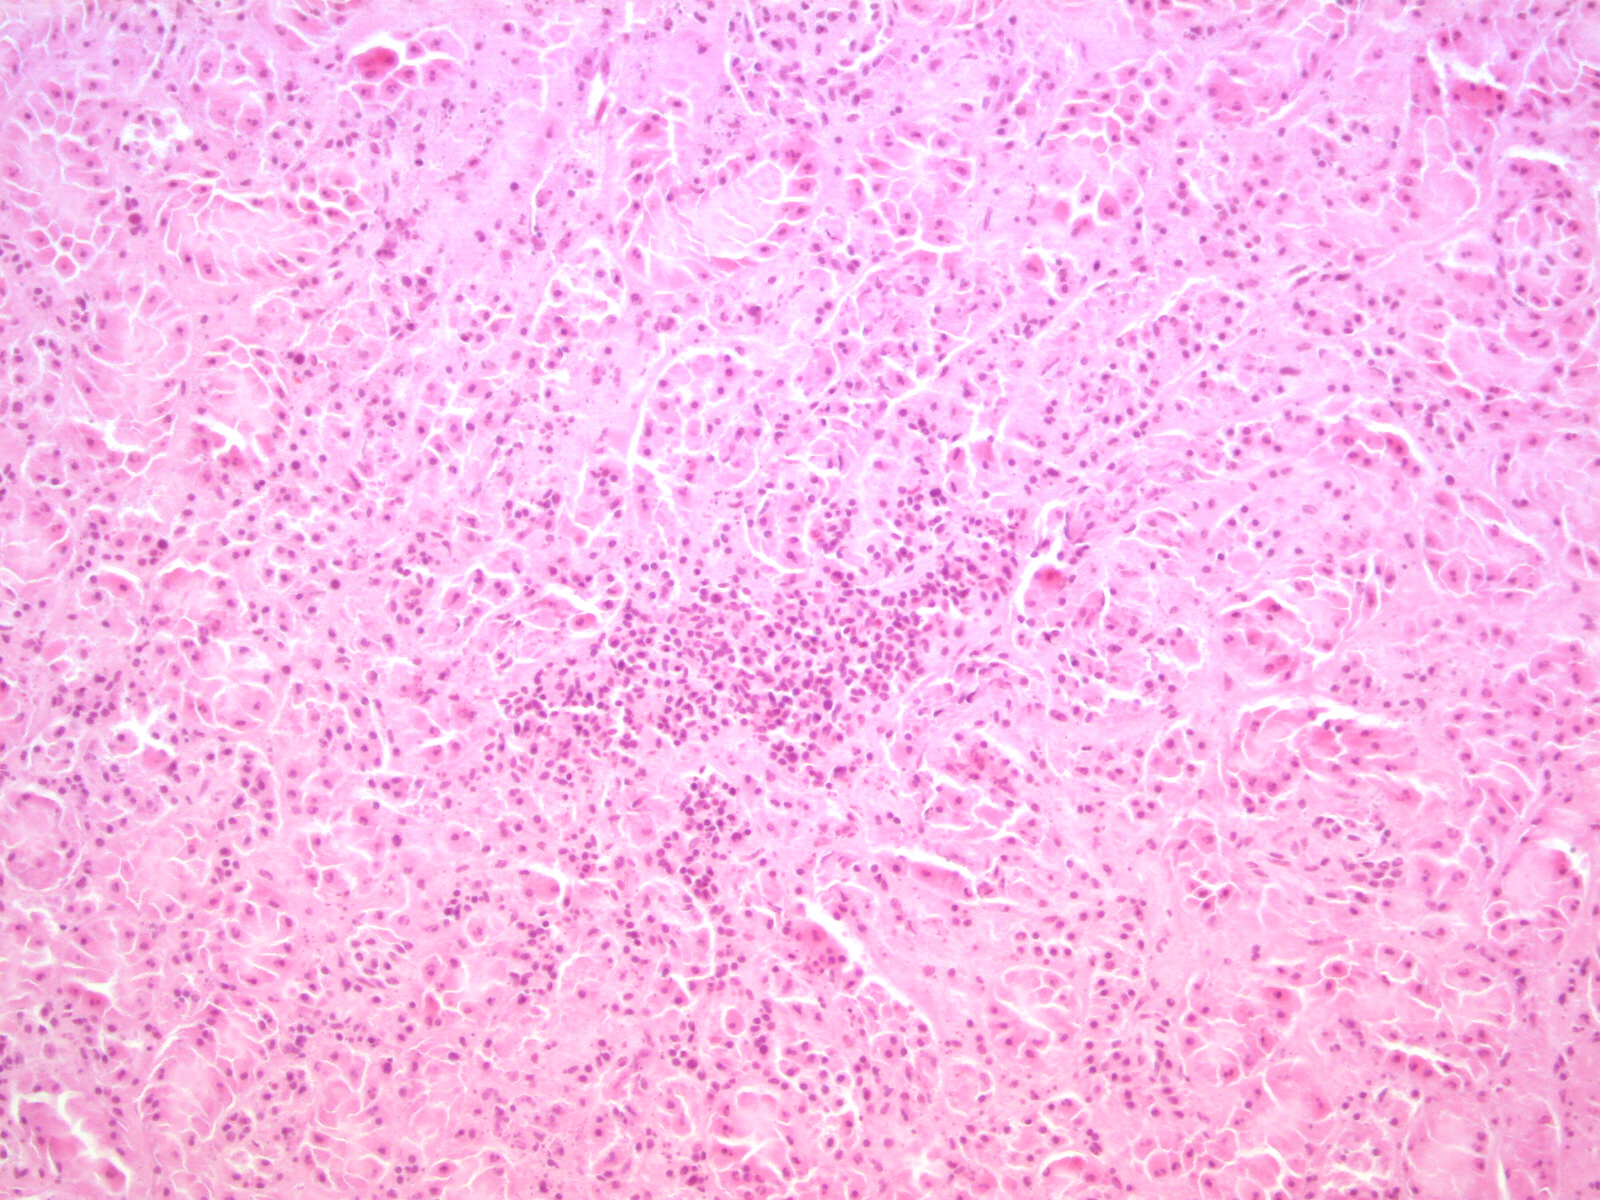

Herkunft und Krankheitsbild

Ursprünglich stammt das Virus aus Afrika und führt vor allem bei Vögeln zu Infektionen. Es ist eng verwandt mit dem West-Nil-Virus, das seit 2018 ebenfalls in Deutschland nachgewiesen wird. Die Übertragung erfolgt durch Stechmücken. Die meisten Vogelarten erkranken nicht. Amseln hingegen scheinen besonders empfänglich zu sein. Die Vögel zeigen zum Teil erhebliche Symptome und sterben in der Folge. Erkrankte Amseln können durch kahles Gefieder, Mattigkeit, Schwanken oder Verdrehen des Kopfes auffallen.